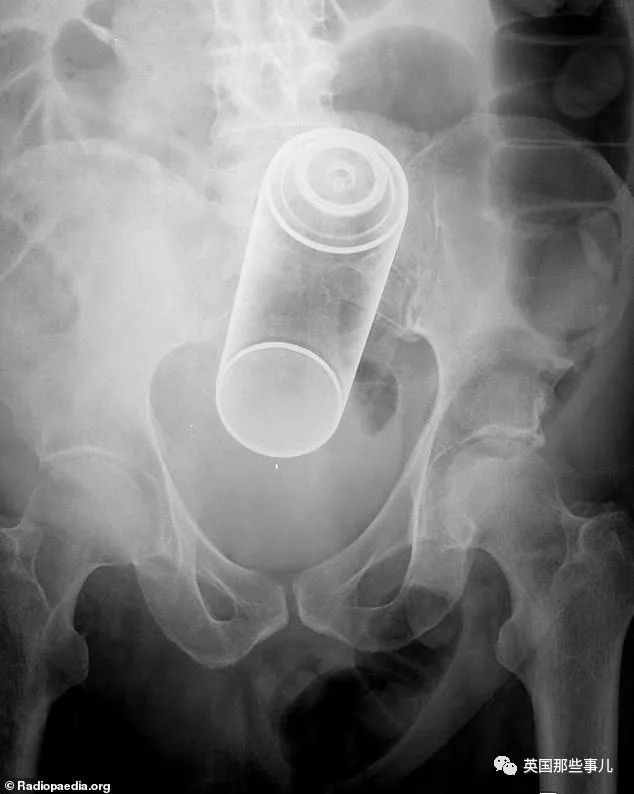

美国人民最喜欢“藏”东西的地方,仍然是直肠……

金属喷雾罐

患者说他在洗手间滑倒了,然后正巧坐在了金属的空气清新剂罐上。